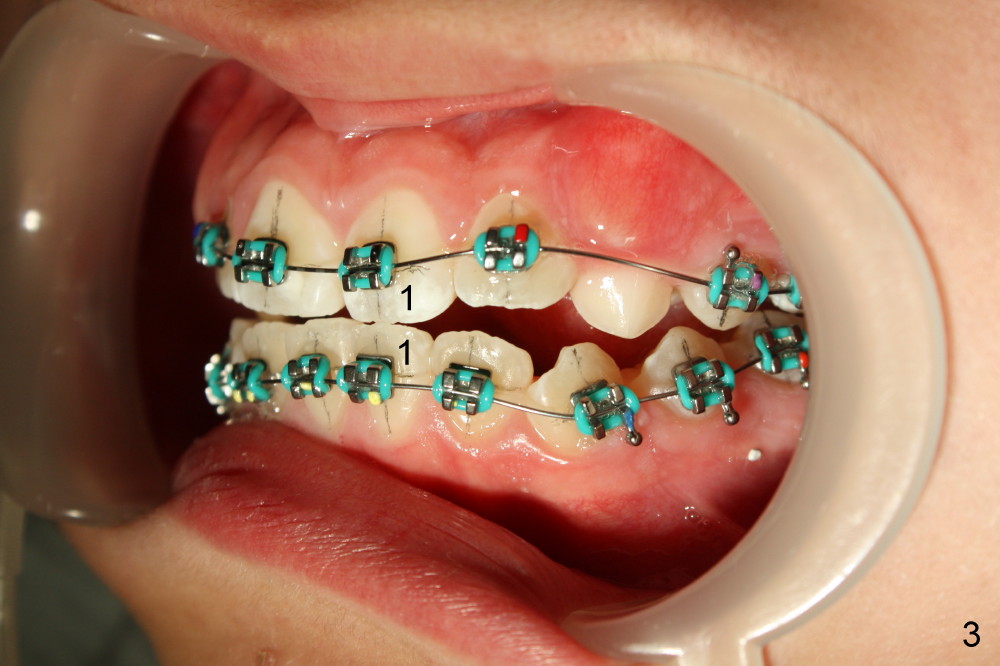

Treatment plan for Nathalie (12 years 9 months old) after banding & bracketing (Visit 1 (Fig.1-3, 7 and 8): use 14 niti)

1. Will the upper anterior teeth erupt more following wire sequence (as wires become straightened, thicker and stiffer, Fig.1)?

2. On bracketing, u1,2s are not level (upper central and lateral incisors, Fig.2).  On Visit 2, 3 or later, they are expected to be at the same level

3. Pre-operatively, the upper and lower anterior teeth edge to edge (Fig.3: u1 vs. l1).  Do we need to add composite on posterior occlusal surfaces for the upper anteriors to move labially?  To be decided on Visit 2

7. Expand spaces for u3s using 18 ss wire until they erupt (Fig.1-3, 7; Visit 3)